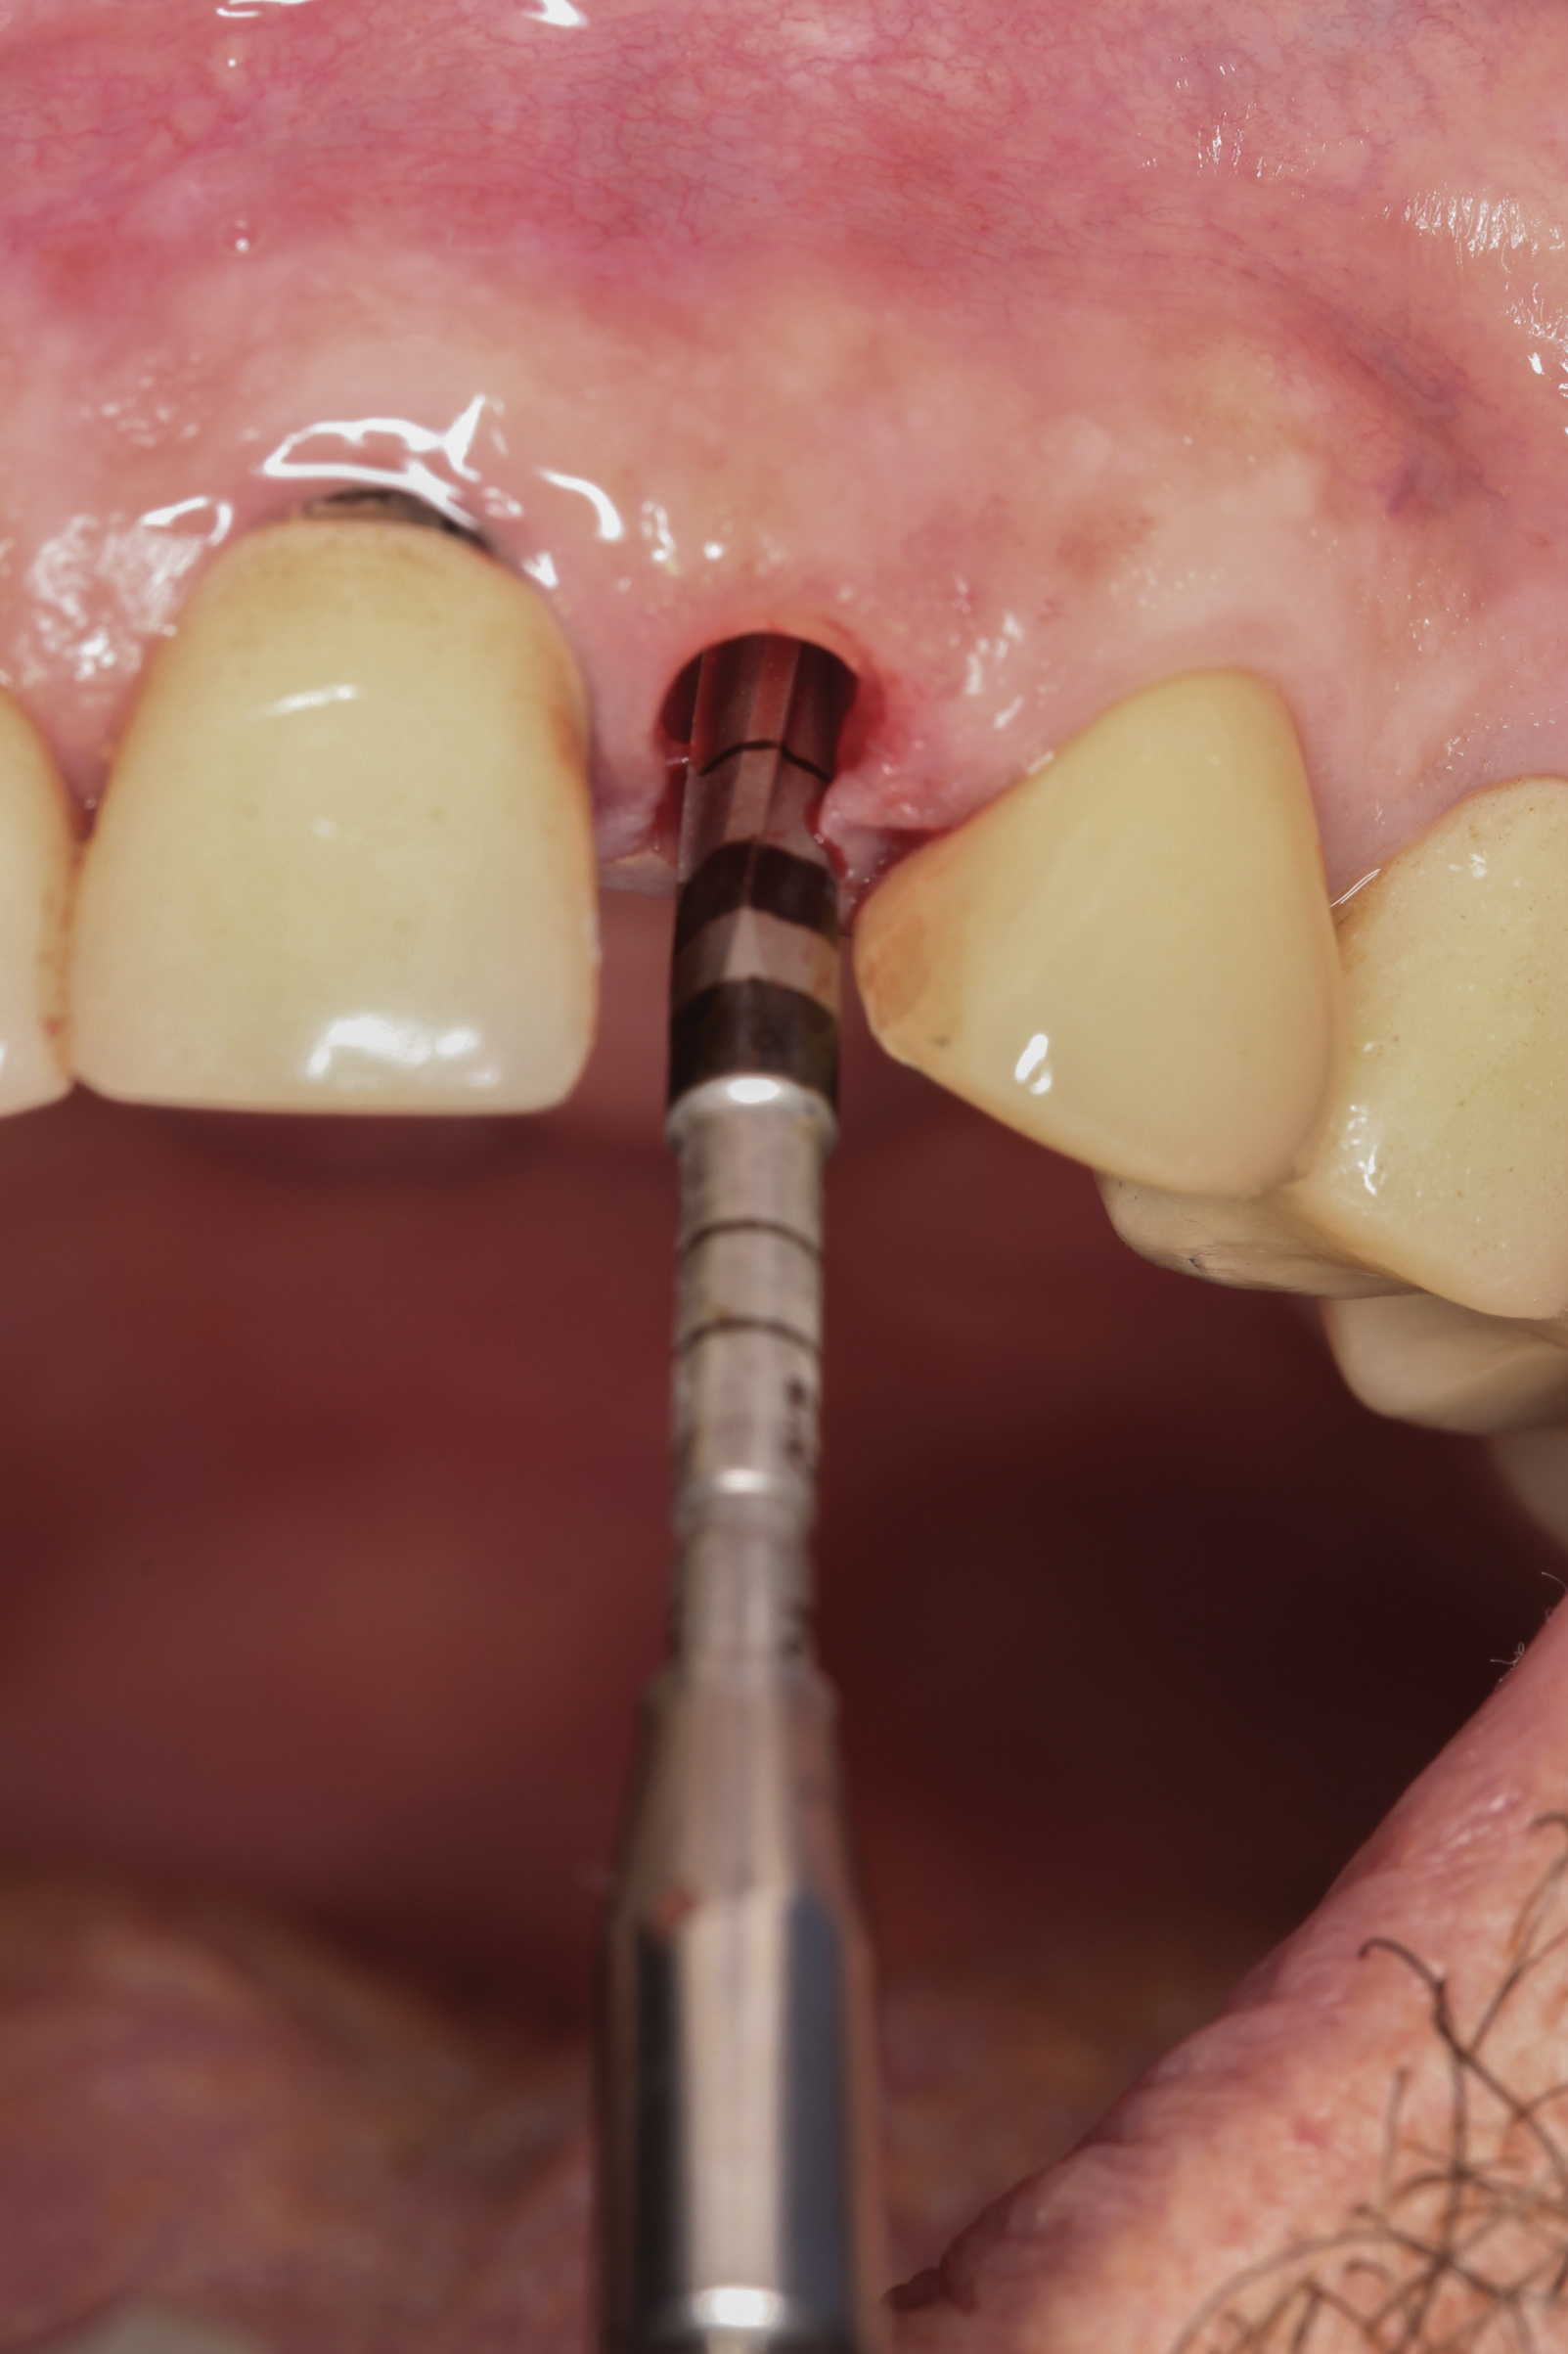

Fig 16. Patient presented with fractured maxillary left lateral incisor. Radiographic analysis (not shown) revealed minimal buccal bone. A socket shield was planned during tooth extraction to preserve gingival contours.

Figure 16

Fig 19. OD burs were used to create implant osteotomy.

Figure 19